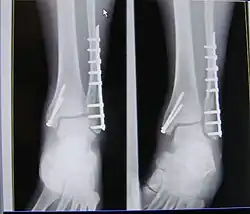

| X-ray of trimalleolar fracture repair before and after ORIF surgery | |

A trimalleolar fracture is a fracture of the ankle that involves the lateral malleolus, the medial malleolus, and the distal posterior aspect of the tibia, which can be termed the posterior malleolus. The trauma is sometimes accompanied by ligament damage and dislocation.[1]

Surgical repair using open reduction and internal fixation is generally required, and because there is no lateral restraint of the foot, the ankle cannot bear any weight while the bone knits. This typically takes six weeks in an otherwise healthy person, but can take as much as twelve weeks. Non-surgical treatment may sometimes be considered in cases where the patient has significant health problems or where the risk of surgery may be too great.[1]